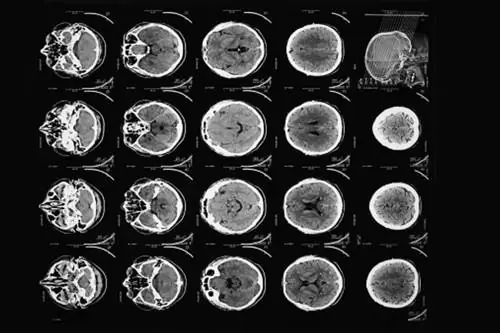

Во-первых, он концептуально разделил бы мозг на последовательные ломтики - как буханку хлеба. Затем он планировал направить серию рентгеновских лучей через каждый слой, повторяя это для каждого градуса полукруга. Сила каждого луча будет фиксироваться на противоположной стороне мозга, причем более сильные лучи указывают на то, что они прошли через менее плотный материал.

Наконец, Хаунсфилд, пожалуй, самое гениальное изобретение, создал алгоритм для реконструкции изображения мозга на основе всех этих слоев. Работая в обратном направлении и используя один из самых быстрых новых компьютеров того времени, он смог рассчитать значение для каждой маленькой коробки каждого слоя мозга. Эврика!

Тем временем Хаунсфилду нужны были пациенты, чтобы опробовать его аппарат. Он нашел неохотного невролога, который согласился помочь. Команда установила полноразмерный сканер в больнице Аткинсон-Морли в Лондоне и 1 октября 1971 года просканировала своего первого пациента: женщину средних лет с признаками опухоли головного мозга.

Это был не быстрый процесс - 30 минут на сканирование, поездка по городу с магнитными лентами, 2,5 часа обработки данных на мейнфрейме EMI и захват изображения камерой Polaroid перед гонкой обратно в больницу.

И это было - в ее левой лобной доле - кистозное образование размером со сливу. При этом любой другой метод визуализации мозга устарел.